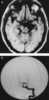

Cysticercus

Cysticercus (pl. cysticerci) is a scientific name given to the young tapeworms (larvae) belonging to the genus Taenia. [Source: Wikipedia ]